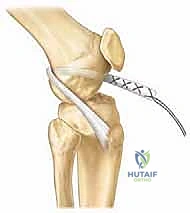

شكل 4: تحديد مسار النفق العظمي بدقة متناهية تحت توجيه الأشعة لضمان بقائه بعيداً عن صفيحة النمو الحساسة.

- إعداد مسار الرباط: بناءً على التقنية المختارة (حفاظاً على صفائح النمو)، يتم تحديد مسار الرباط الجديد بدقة باستخدام أجهزة تصوير إشعاعي داخل غرفة العمليات (Fluoroscopy).

- تمرير وتثبيت الطعم: يتم إدخال الرباط الجديد وتثبيته بقوة باستخدام أزرار معدنية أو مسامير طبية خاصة لا تعيق النمو.

شكل 8: استخدام الأشعة السينية (Fluoroscopy) أثناء الجراحة (Intraoperative) لتأكيد الموقع الدقيق للأنفاق العظمية وأدوات التثبيت والتأكد من عدم مساسها بصفائح النمو.